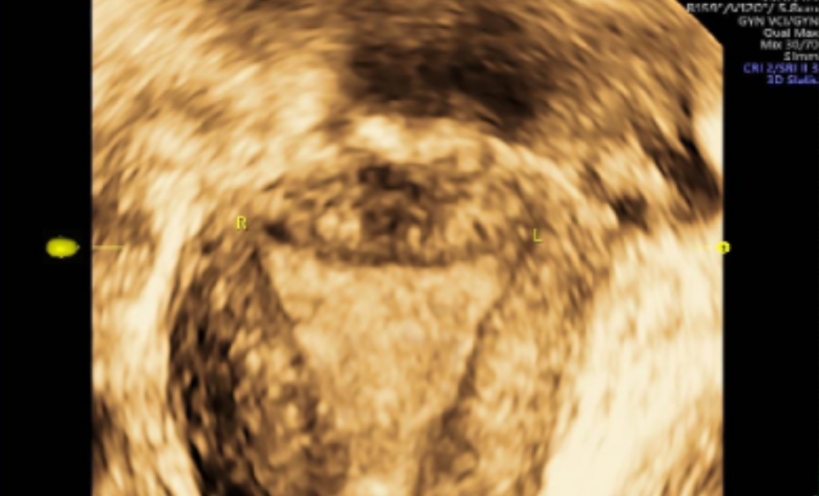

一位处于育龄阶段的女性,其健康状况让人担心。2024年5月24日,是她最后一次来月经的日子。在月经第20天的时候,做了四维彩超,结果显示出不少问题。内膜厚度不均匀,下段大约是2.3mm,中段约为3.1mm,上段约4.7mm。内膜的这种情况不太好,这为后续的诊断以及治疗埋下了隐患。

此次检查发现了其他病症,除了之前提到的宫腔粘连和节育器问题。四维彩超显示,子宫后壁下段有稍高回声结节,怀疑是子宫腺肌瘤。子宫前壁下段有低回声结节,考虑是子宫肌瘤(5型)。诊断已经明确,病情比较复杂,多种病症同时存在。